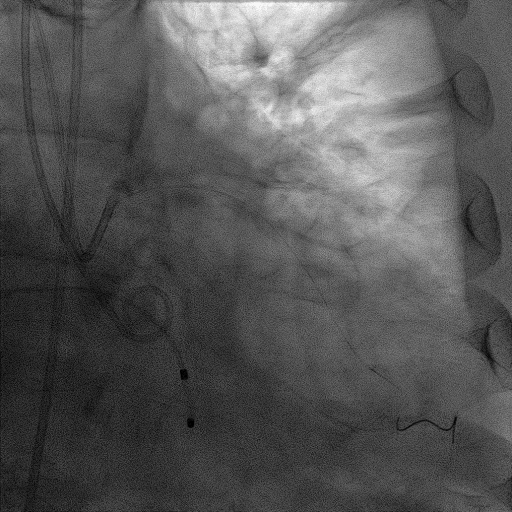

74岁男性,因活动后胸闷憋气如我院,超声提示主动脉瓣狭窄,STS评分12.3%,经心脏团队讨论有行冠脉造影检查及TAVR指证。

术前CT

CT提示为该患者三叶瓣,右无轻度融合,冠脉开口高度尚可,窦部空间可,髂总动脉近环形钙化,内径可,计划予以23mm球囊扩张,植入Venus A 26瓣膜。

手术过程

CAG:LAD近中段弥漫钙化,近段80%狭窄,中段90%狭窄,D190%狭窄,中间支近段90%狭窄,右冠近中段弥漫病变,最重狭窄50%。考虑患者胸痛症状可能为冠心病+AS共同作用,以及患者冠脉病变钙化严重,予以旋磨+PCI+TAVR一站式处理。